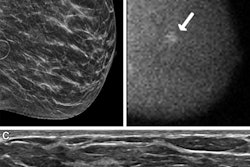

MBI uses a small-field-of-view gamma camera to image radiotracer uptake within the breast, and it is used as a supplement to screening with standard digital mammography or to guide treatment. Previous research suggests that MBI has a supplemental cancer detection rate of eight to nine cancers per 1,000 women screened when used along with digital mammography.

Breast radiologists developed a lexicon in 2012 for MBI that mirrors the lexicon used for imaging descriptors in the BI-RADS atlas. This lexicon includes descriptors for mass versus nonmass radiotracer uptake, distribution of nonmass uptake, and lesion intensity.